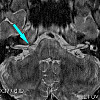

МРТ черепных нервов (1 пара)

МРТ черепных нервов (1 пара) представляет собой технологию получения объемных и послойных изображений черепных нервов и прилегающих к ним структур, основанную на регистрации и преобразовании электромагнитных колебаний, излучаемых ядрами атомов водорода во внешнее магнитное поле. сильный. Метод диагностики направлен на визуализацию структуры и выявление патологических изменений в черепных нервах. Может использоваться для выявления очагов демиелинизации, опухолей (невромы, менингиомы), воспалительных заболеваний, цереброваскулярных заболеваний, сдавления корней. Магнитно-резонансная томография черепных нервов начинается со стандартного исследования мозга. Далее, специальный протокол используется для изучения части цистерны FMN. Следующим шагом является магнитно-резонансная томография с контрастным усилением для устранения вазоневрального конфликта.